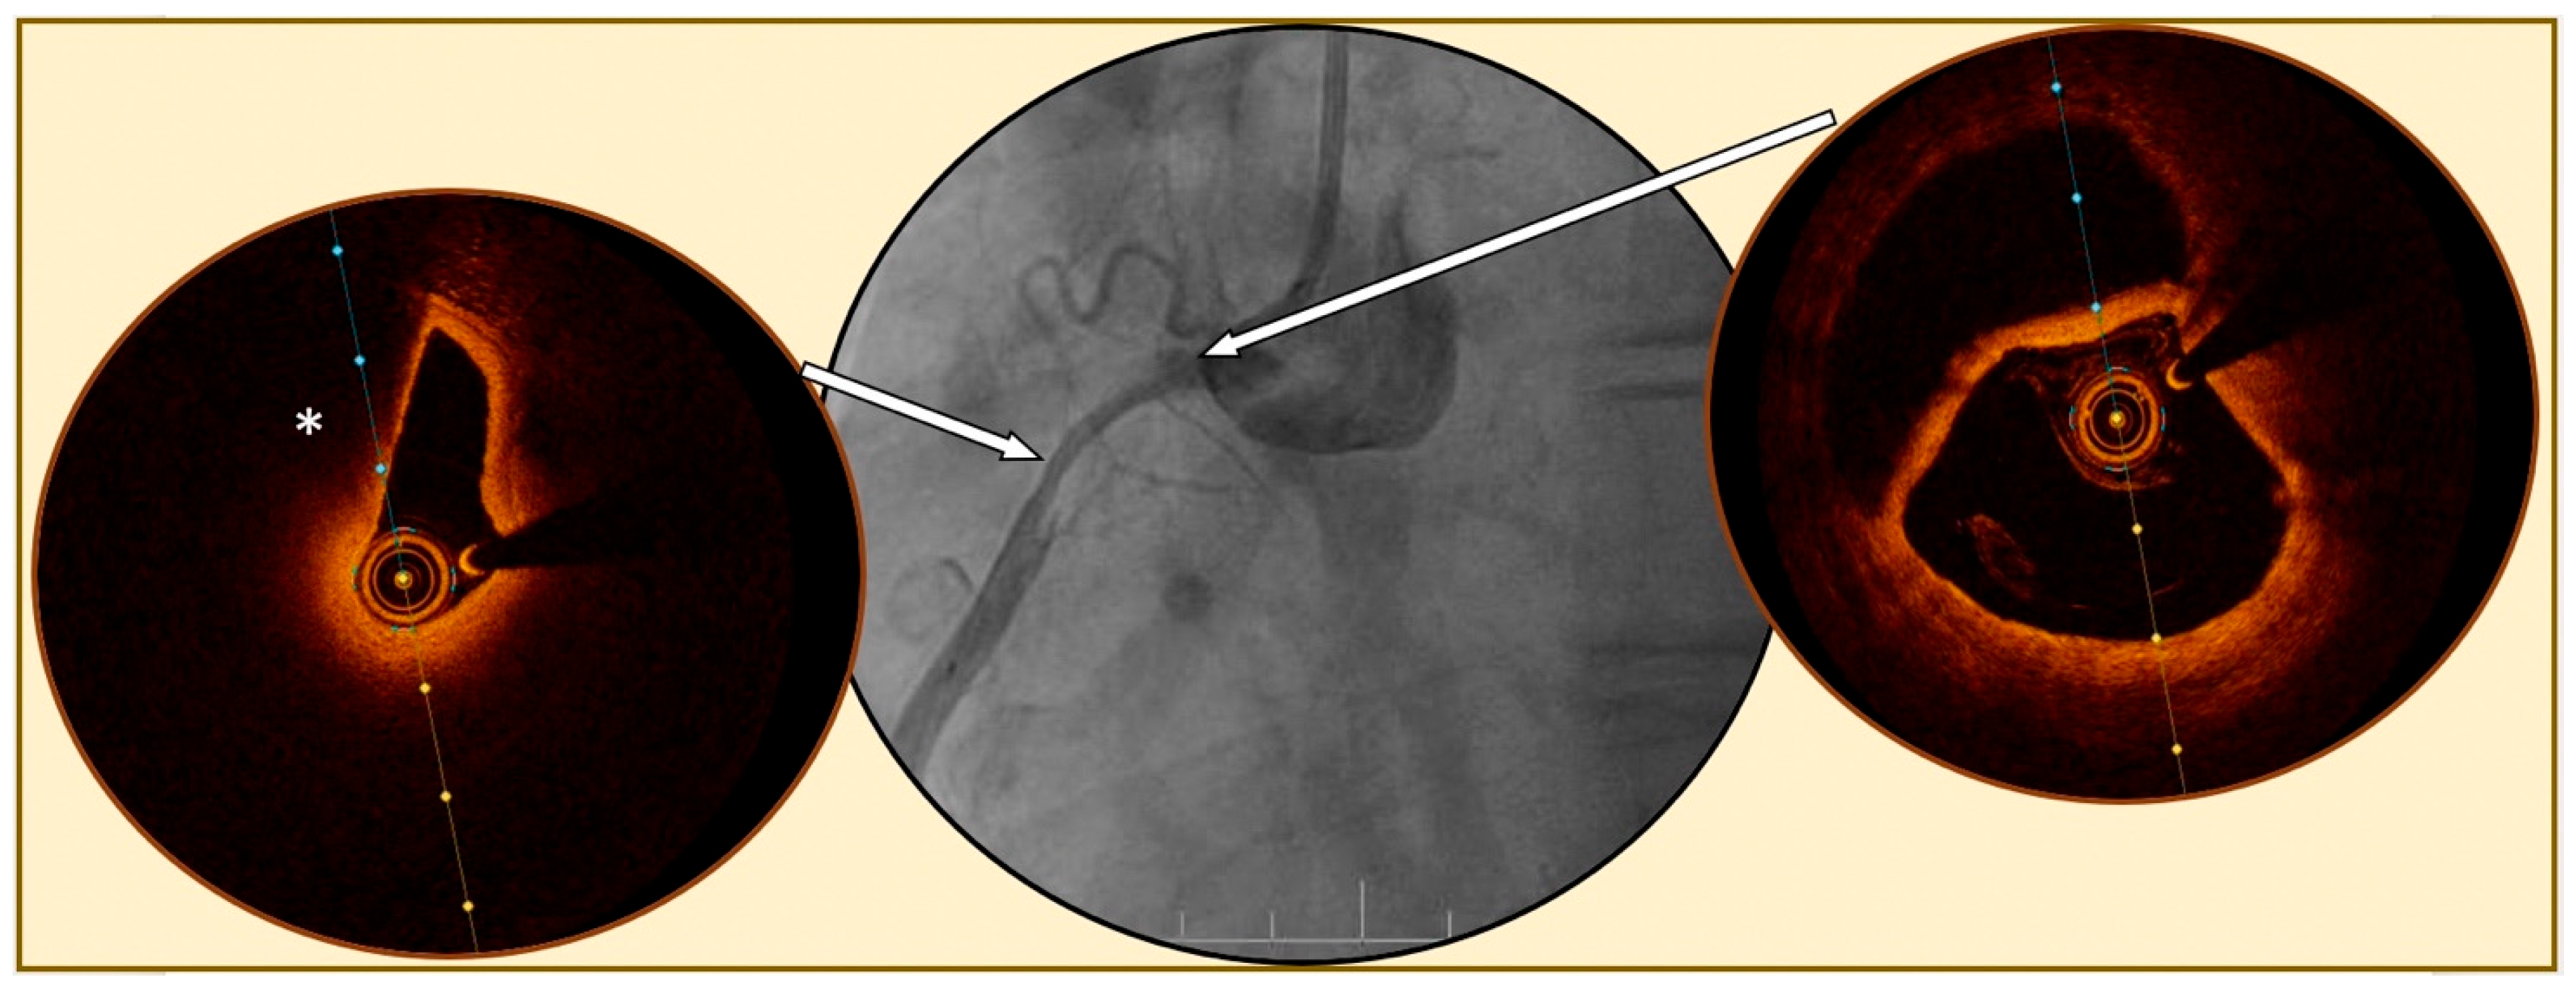

Figure 3.

Spontaneous coronary artery dissection evaluated by optical coherence tomography. Legend: Angiography of a right coronary artery (central figure) showing a diffuse tabular narrowing highly suspected for spontaneous coronary artery dissection. Optical coherence tomography (OCT) images confirm the diagnosis of a large dissection, with the presence of a false double lumen (right figure), at the beginning of the dissection (right arrow) and compression of the true lumen (left figure) by a diffuse circular hematoma (*) in the mid lesion (left arrow).